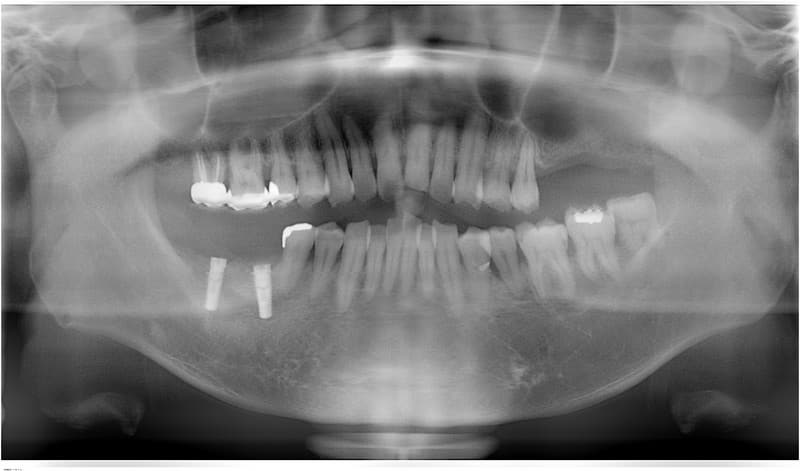

- 外科処置によって顎の骨にインプラントを埋め込みます。

- 3~6ヶ月後にインプラントに人工の歯を連結するためのパーツを取り付けます。

人工の歯をインプラントに連結して完成となります。